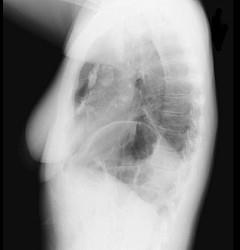

问题 71岁,女,发现颈部淋巴结肿大,胸片和CT检查如图,请选出最可能的诊断 ( )

选项 A、肺癌 B、神经源性肿瘤 C、淋巴瘤 D、淋巴结核 E、结节病

答案 C